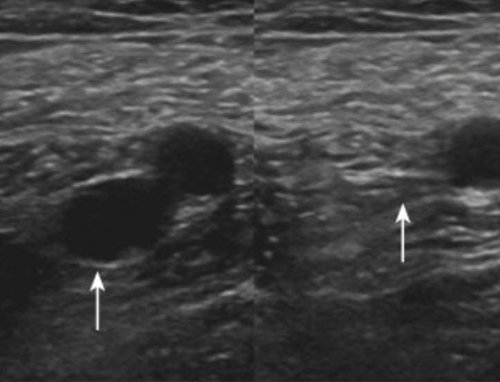

Outcomes observed in patients treated with image-guided, minimally invasive vascular procedures.

Results vary by patient and condition. Images are for educational purposes only.